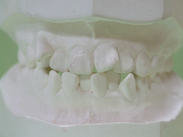

A.子供の歯並びや不正咬合の予防に関して、相談や効果的な指導及び、咬合育成を行っています。この小児矯正のすべて症例はハーバード大学臨床教授の宮嶋先生のセカンドオピニオンが付いています。 B.できる限り大人の歯(永久歯)を抜かないで、顎の発育を利用します。 C.前方から装置が目立たない矯正治療すなわち舌側矯正やクリアブラケットを用い、審美的な改善を主眼にしています。 D.セントルイス大学大学院の矯正学コースにて習得した改良されたブラケットであるティップエッジブラケットや歯に優しいデーモンシステムなどを採用しています。 E.希望があればミニインプラントを用い牽引し治療期間を短くします。 |